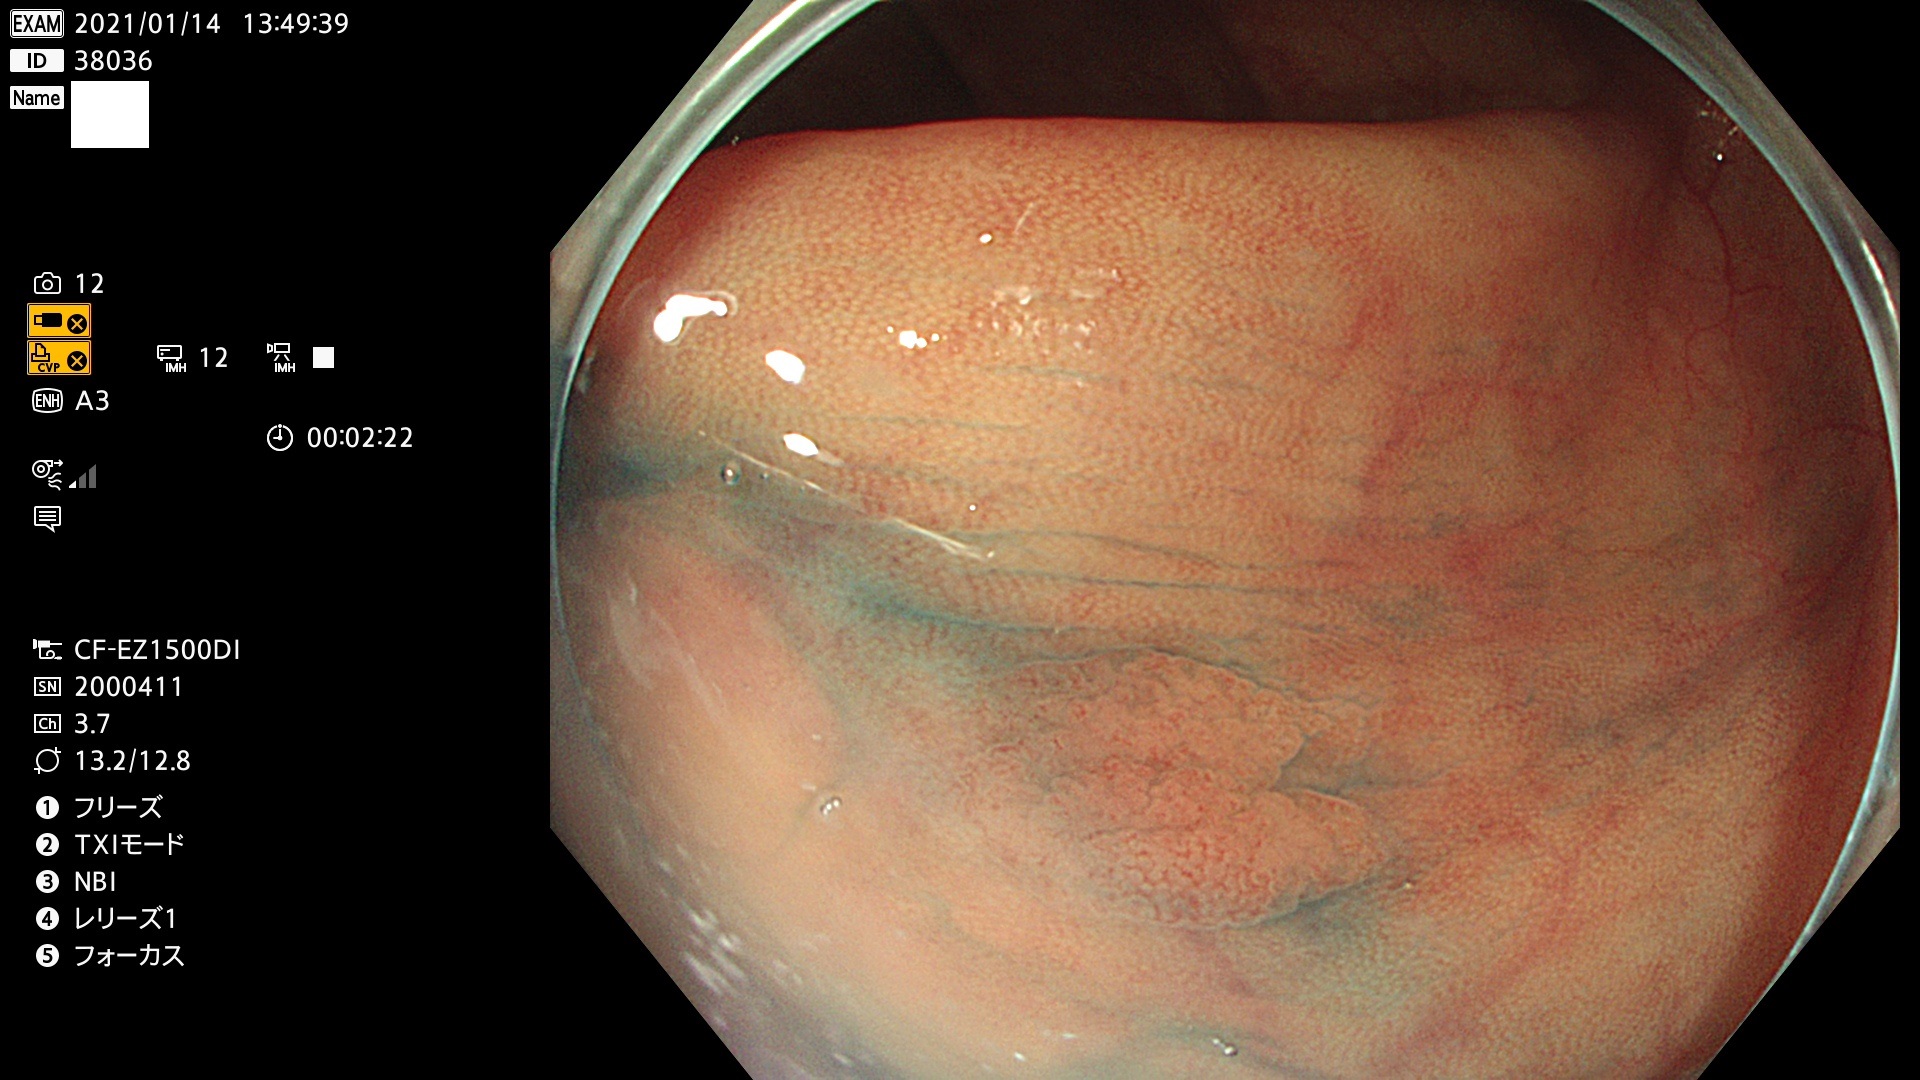

38001 38002 38003 38004 38006(SSAPのみ) 38007 38008 38009 38010 38012 38013 38014 38016 38018 38020 38021 38025 38026 38029 38032 38033 38034 38035 38036 38037(SSAPのみ) 38039 38043 38044 38048 38049 38050 38052 38055 38056 38057 38058 38059 38064(SSAPのみ) 38065 38068 38069 38070 38071 38072 38074 38075 38076 38078 38079 38080 38082 38083 38084 38085(SSAPのみ) 38086 38087 38088 38089 38090 38091 38092 38093 38094 38097 38098 38099

発見困難で危険性の高い平坦型病変(上記100名より抽出)